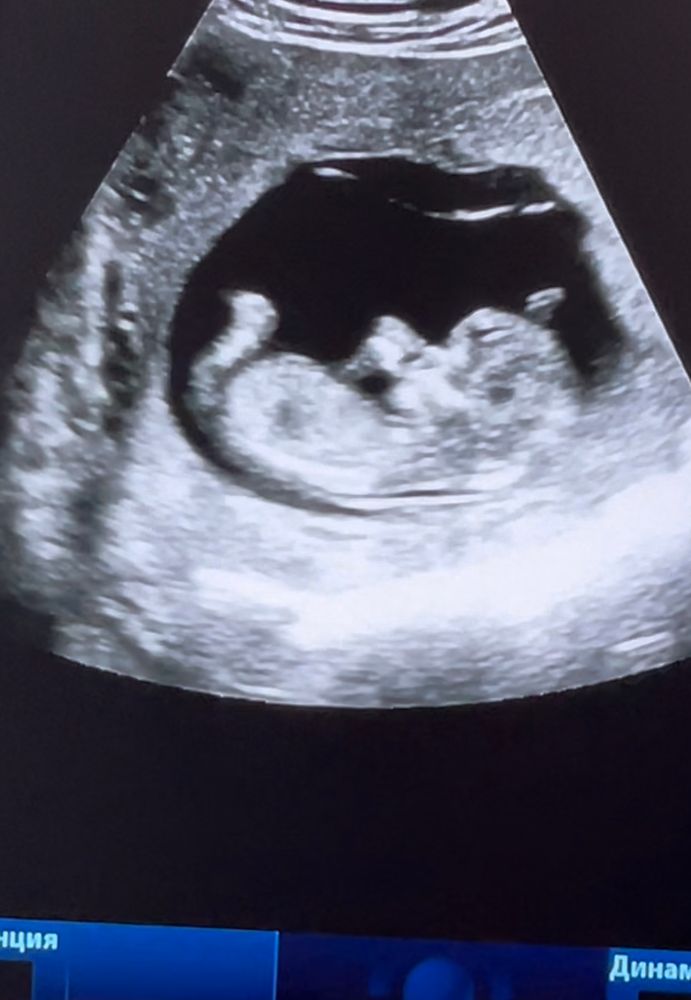

13 недель💙 Узи🔥

Вчера тоже ходила и тоже такой уже большенький был 🙈 аж не верится но я 4 апреля на скрининг, там все замеры будем делать